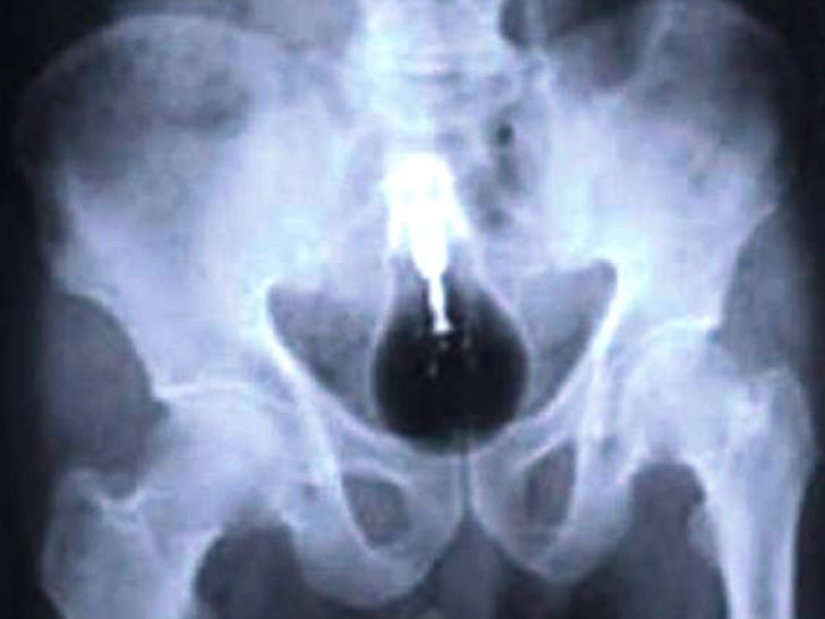

Y esta es la foto de un hombre que ingirió una cantidad considerable de drogas para traficarlas a través de la frontera.